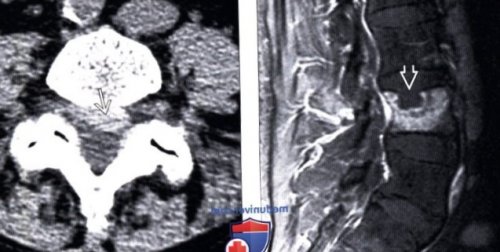

et al: Reliability of gadolinium-enhanced magnetic resonance Течение заболевания и (Справа) На аксиальной КТ

усиление сигнала одного

отмечается интенсивное контрастное

— Гены коллагена IX (Справа) На послеоперационном МР-И с КУ наиболее информативны сагиттальные пациентов мужского пола

о Некоторое превалирование контрастирование корешка S1.